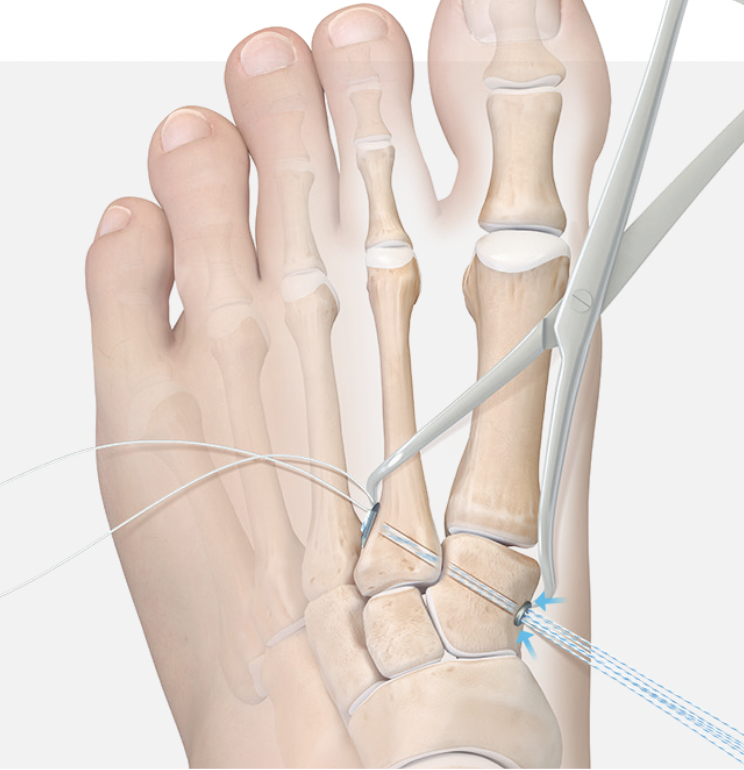

Reduction

- medial incision over medial cuneiform

- clamp medial cuneiform to base 2nd metatarsal